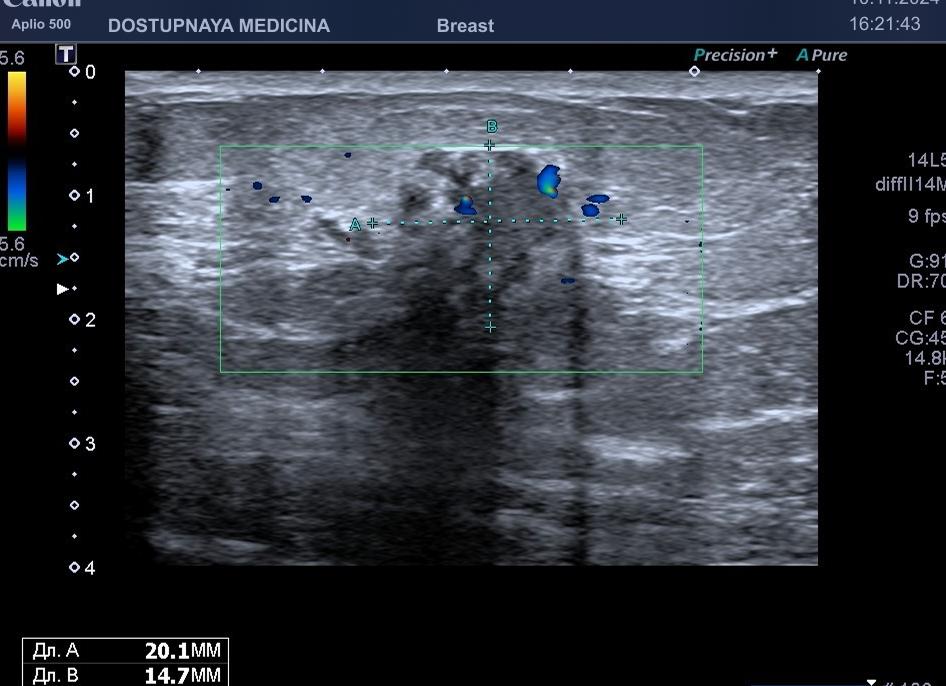

Ультразвуковая диагностика раковой опухоли простаты

Самой характерной приметой рака простаты является гипоэхогенный очаг на периферическом участке предстательной железы. Таких очагов может быть большое количество. Некоторые заболевания органа также способствуют возникновению гипоэхогенных зон: атрофия простаты, воспалительный процесс, острый простатит, туберкулез и пр. Поэтому для установления характеристики гипоэхогенного очага требуется проведение биопсии.